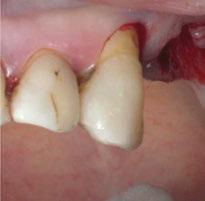

Para ilustrar el proceso, presentamos el caso de una mujer joven diagnosticada de carcinoma adenoide quístico en la región posterior del hemipaladar izquierdo (Figuras 1 y 2). El procedimiento quirúrgico realizado fue una

maxilectomía parcial que incluyó las piezas 24-26 y desde el reborde alveolar hasta la base del cráneo (Figuras 3 y 4). En este caso, la órbita y el globo ocular pudieron ser preservados. La reconstrucción inmediata se realizó mediante un colgajo de músculo temporal homolateral (Figura 5) y el defecto de la fosa temporal fue cubierto mediante una malla de titanio. Posteriormente, la paciente recibió radioterapia (Figuras 6 y 7). 2 años más tarde se diseñó un IS con anclaje en el arbotante nasomaxilar, zona subnasal izquierda

Figura 1. Imagen preoperatoria de la paciente.

Figura 2. Carcinoma adenoide quístico en región posterior del hemimaxilar izquierdo.

Figura 3. Maxilectomía parcial.

Figura 4. Defecto maxilar tras resección del tumor.